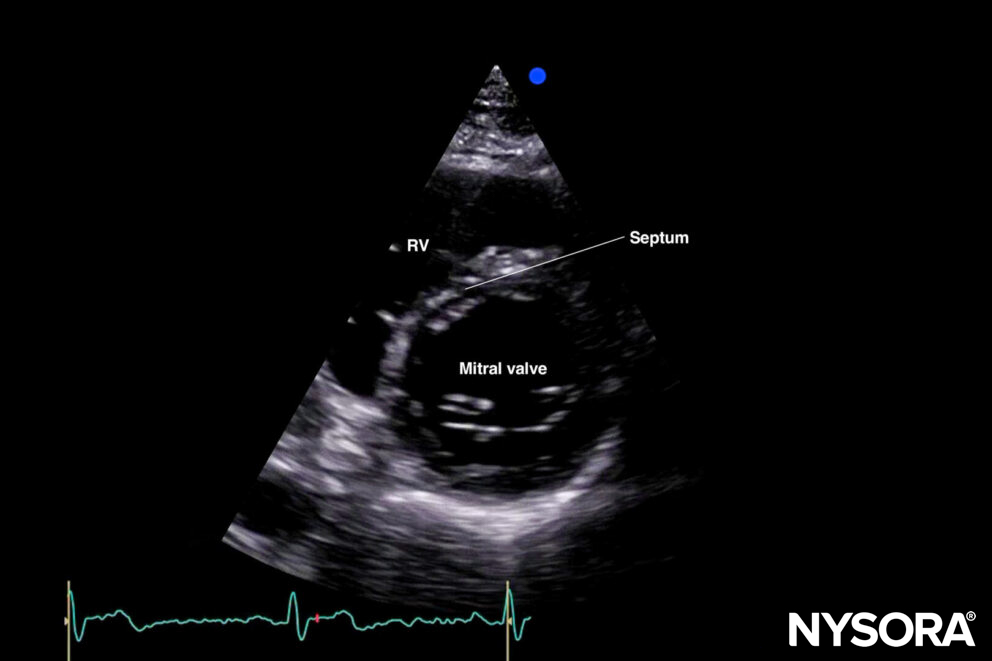

The standard parasternal short-axis view cuts the heart through the transverse plane.

Sonoanatomy of the heart in the parasternal short-axis view. Right ventricle (RV), septum, left ventricle (LV), and papillary muscles.

Reverse ultrasound anatomy:

Reverse Ultrasound Anatomy of the heart in the parasternal short-axis view. Right ventricle (RV), septum, left ventricle (LV), and papillary muscles.